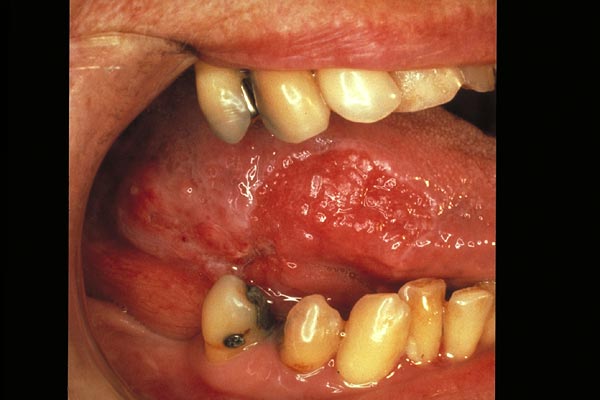

Zungencarcinom

|

Candidose

Leukoplakie